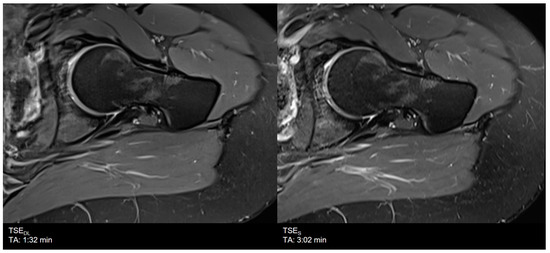

| Hip | TSES | TSE PD FS | axial | 3:02 | 200 | 0.3 × 0.3 × 3.0 | 1 | 1 | 0 | 3410 | 42 | 150 | 100 | 14.1 |

| coronal | 2:01 | 200 | 0.3 × 0.3 × 3.0 | 1 | 1 | 2 | 3410 | 42 | 150 | 100 | 14.1 | |||

| TSEDL | TSE PD FS | axial | 1:32 | 200 | 0.6 × 0.6 × 3.0 | 1 | 1 | 3 | 3069 | 42 | 150 | 120 | 13.1 | |

| coronal | 1:33 | 200 | 0.6 × 0.6 × 3.0 | 1 | 1 | 3 | 3000 | 41 | 150 | 120 | 13.7 | |||